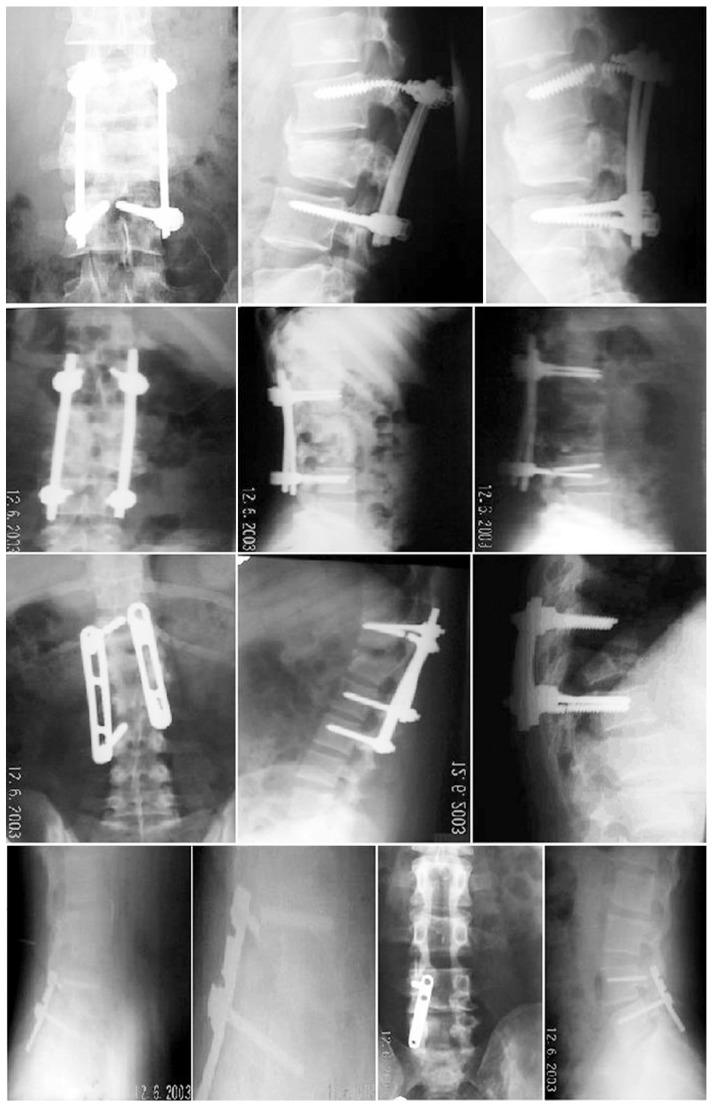

Two hundred patients (88 women, 112 men) were divided into 2 major groups, with 100 patients in group I (implant failure group G1) and 100 patients in group II (successful fusion, control group G2). We subdivided the study groups into two subgroups: subgroup a (single-level instrumented group) and subgroup b (multilevel instrumented group). The implant status was assessed based on intraoperative and follow-up radiographs.

Implant failure in general was present in 36% in G1a, and in 64% in G1b, and types of implant failure included screw fracture (34%), rod fracture (24%), rod loosening (22%), screw loosening (16%), and failure of both rod and screw (4%). Most of the failures (90%) occurred within 6 months after surgery, with no reported cases 1 year postoperatively.